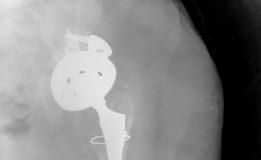

History of presenting complaint : This is the case of a patient with a history of slipped capital femoral epiphysis that initially had a left total hip arthroplasty in 1985 at the age of 39 for degenerative joint disease and acetabular protrusio secondary to rheumatoid arthritis. This total hip replacement functioned well for 25 years until it was revised in 2010 for aseptic loosening of the acetabular shell. At the time of her first revision in 2010, she was found to have a Paprosky type IIC defect, and this was revised with bone grafting and placement of a large cup with six screws and an eccentric liner, while the femoral component was left in place. In 2013, she presented to the clinic with left hip pain and mechanical failure of the acetabular component. Radiographs and CT scan revealed a Paprosky type IIIB defect of the acetabulum with a >3 cm superior migration of the hip centre, ischial osteolysis, and violation of Kohler’s line with obliteration of the teardrop (Fig. 19.7).

Preoperative Radiological Assessment/Imaging(Figs. 19.7, 19.8, and 19.9)

Diagnosis : Aseptic failure of revision total hip arthroplasty with Paprosky type IIIB acetabular defect (Fig. 19.7).